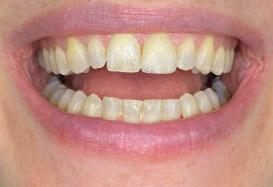

Timothy Zoltie is Head of the Medical & Dental Illustration Department, based within the School of Dentistry at the University of Leeds, in a collaborative role with Leeds Teaching Hospitals NHS Trust. He is an award-winning professional photographer and videographer, in the speciality area of medicine and dentistry. A Fellow of the Institute of Medical Illustrators, as well as a Fellow of the Royal Photographic Society, Timothy Zoltie also works as Editor in Chief of the Journal of Visual Communication in Medicine.

The School of Dentistry at the University of Leeds stands as a preeminent hub for dental education and research, distinguished by its expert faculty and state-of-the-art training facilities. Renowned as a leading centre for dental study, the school is committed to shaping the future of dentistry by nurturing the skills of the next generation of dental professionals. A unique element of the institution is that it has a dedicated Dental Photography Department, one of only a few in the world. The dental photography department at the University of Leeds has been delivering high-quality dental photography services for over 60 years, and currently photographs over 8,000 patients per year.

In reviewing the market for camera systems to use for dental and clinical photography, Timothy was looking for a compact solution that would capture the highest-quality images, while offering versatility to shoot stills and video.

solution and results

After reviewing the various options, Timothy chose the Sony Alpha a7R V Mirrorless camera system. In capturing stills and video, the camera provides the versatility Timothy was looking for in his hybrid role, where he not only photographs clinical conditions but also undertakes clinical videography. The seamless interchangeability of lenses for video and stills on a single system significantly enhances workflow efficiency. The compact form factor of Sony cameras improves manoeuvrability and user comfort, which is particularly advantageous for repetitive tasks such as intra-oral photography. Manual focusing for Timothy is crucial in dental

photography for maintaining consistent working distances and is facilitated by the Sony 90mm Macro G OSS lens. It is the only mirrorless lens in its focal range equipped with lens distance scales and ratios on the barrel.

“The Sony FE 90mm Macro G is one of the sharpest macro lenses I have used, Timothy explains. “Clarity is imperative when undertaking clinical photography and paired with a high-resolution camera such as the Sony Alpha 1 or Sony Alpha a7R V, it allows exceptional documentation of clinical detail.”

When Timothy is shooting in clinical conditions, where stopped-down apertures of f/22 are used for increased depth of field, effective lighting is crucial. Flash is the key source of illumination and the Godox MF-R76S+ Ring Flash developed jointly with Sony Europe is used with the Sony Alpha camera. This dedicated dental kit is easy to set up and delivers the required picture quality in combination. The optimised dental kit compatibility for Sony Alpha cameras provide highly accurate E-TTL functionality that produces the correct exposure on every shot, regardless of camera-tosubject distance.

Another camera feature Timothy uses is custom modes. This enables standardised settings for specific tasks, streamlining workflows and minimising errors. For example, custom mode 1 can be assigned for intraoral photography, and custom mode 2 can be designated

t imothy recommends that other dental professionals considering using sony alpha cameras should test the kits that fit their practice, explore the system’s versatility, and invest in dental photography training.

He said: “take time to understand the camera’s features and functionalities to unlock the full potential of the camera, such as how to calibrate and set up custom modes, and how to switch between them. Once calibrated, the sony system paired with the dedicated Godox MF-R76s+ for sony alpha cameras is by far one of the easiest camera set ups for dental photography and can be used by any of the dental team.”

for videography, with all the associated settings for each mode saved.

The adoption of Sony Alpha cameras at the University of Leeds has significantly elevated the quality and efficiency of dental photography and videography. Timothy Zoltie’s experience highlights the importance of a versatile and user-friendly camera system in the specialised field of dental imaging.

Timothy said: “Choosing a hybrid system has proven very advantageous, seamlessly facilitating the interchangeability of lenses for

both video and stills. This versatility enables me to effortlessly transition between filming surgical procedures and undertaking commercial healthcare photography commissions for marketing agencies or NHS institutions.

“The Sony Alpha cameras’ hybrid functionality, complemented by features such as manual focusing and custom modes, makes them ideally suited to dental photography and they have become indispensable assets for documenting clinical procedures and conditions at the School of Dentistry.” n www.masteringdentalphotography.com